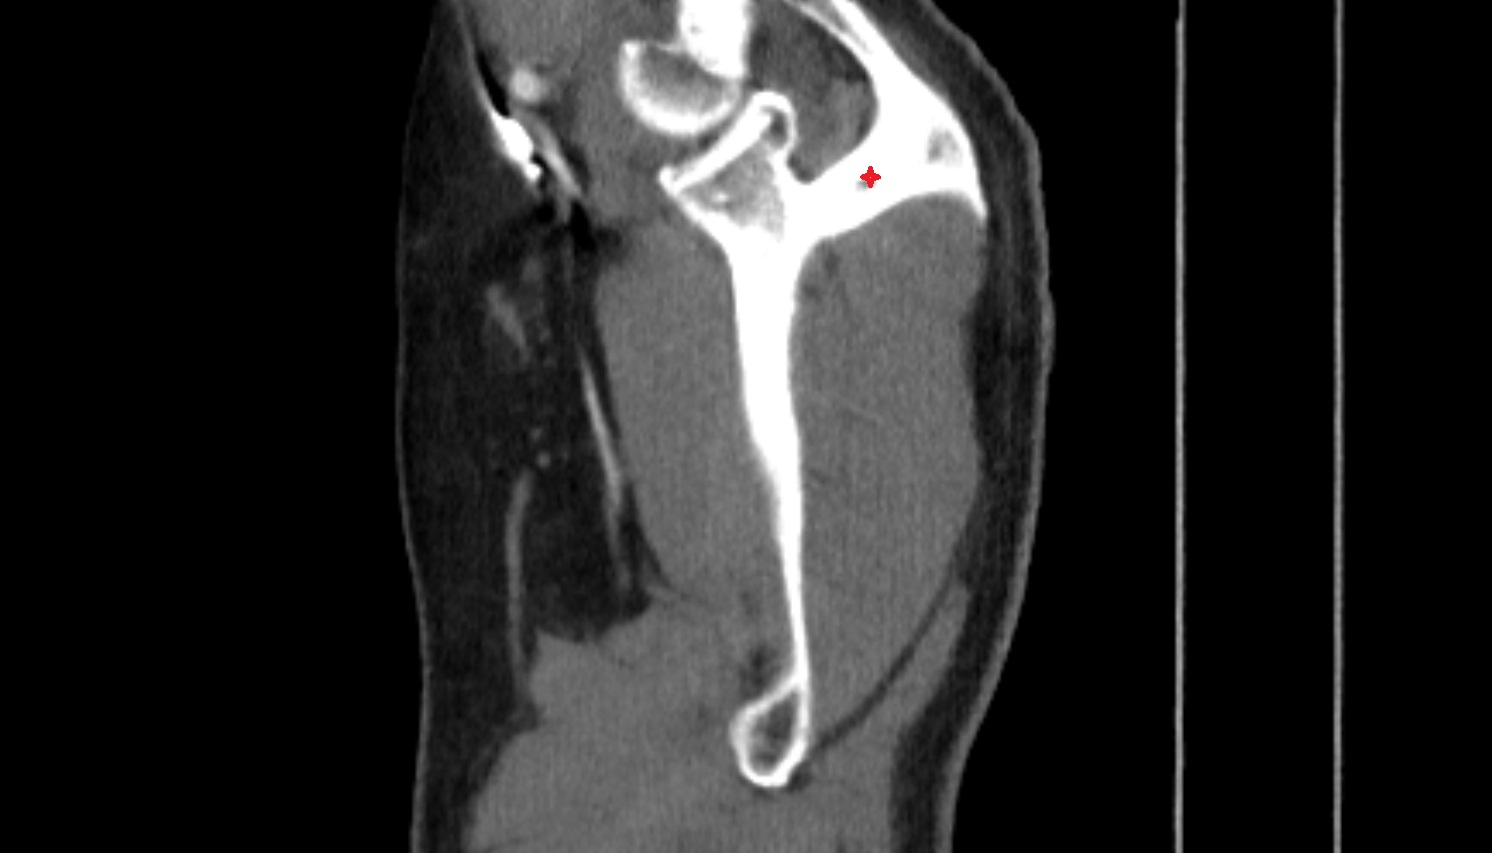

- Glenoid fossa

- Glenoid process of scapula

- Spine of scapula

- Acromion process of scapula

- Coracoid process of scapula

- Scapular body

- supraspinous fossa of scapula

- Subscapular fossa

- Neck of scapula

- Humerus

- Head of humerus

- Body of humerus